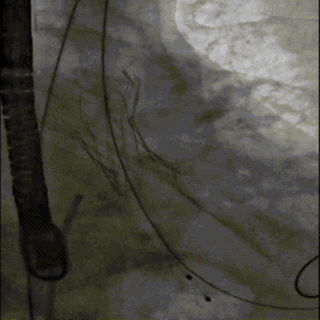

选择22mm球囊进行预扩,结果显示具有明显腰征,无瓣周返流,随即选择TaurusElite26mm瓣膜,凭借其优异的柔顺性,轻松完成过弓。